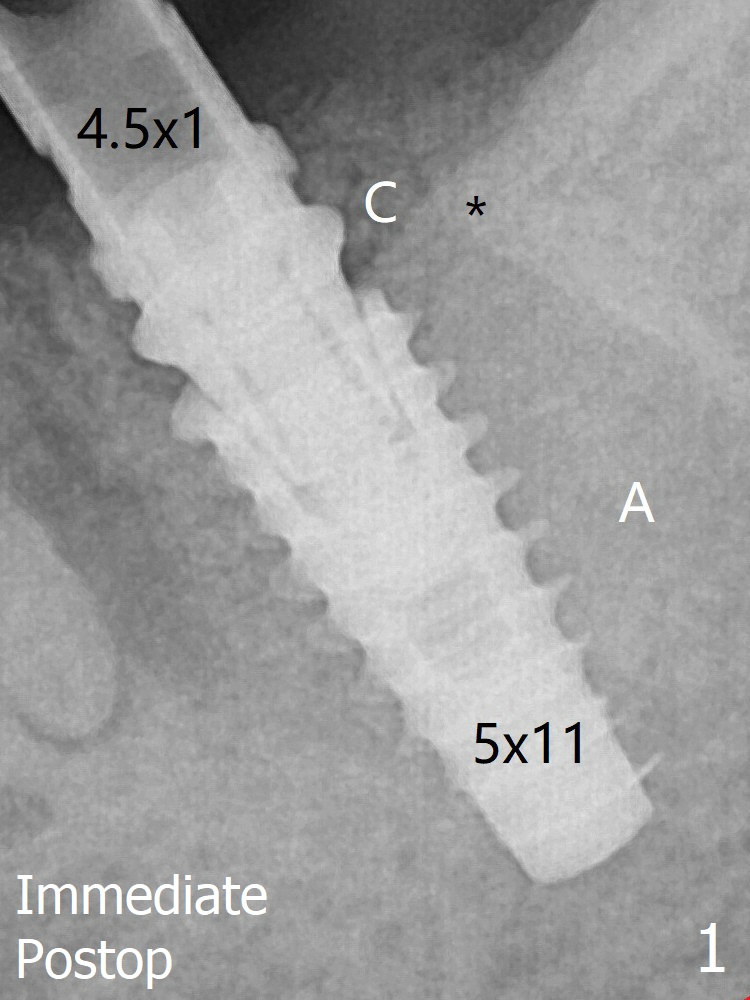

The implant seems to remain non-osteointegrated 3.5 months postop (Fig.9).  Later a 6.8x4 mm healing abutment is placed with occlusal clearance.  X-ray will be taken every 2-3 months until osteointegration occurs.